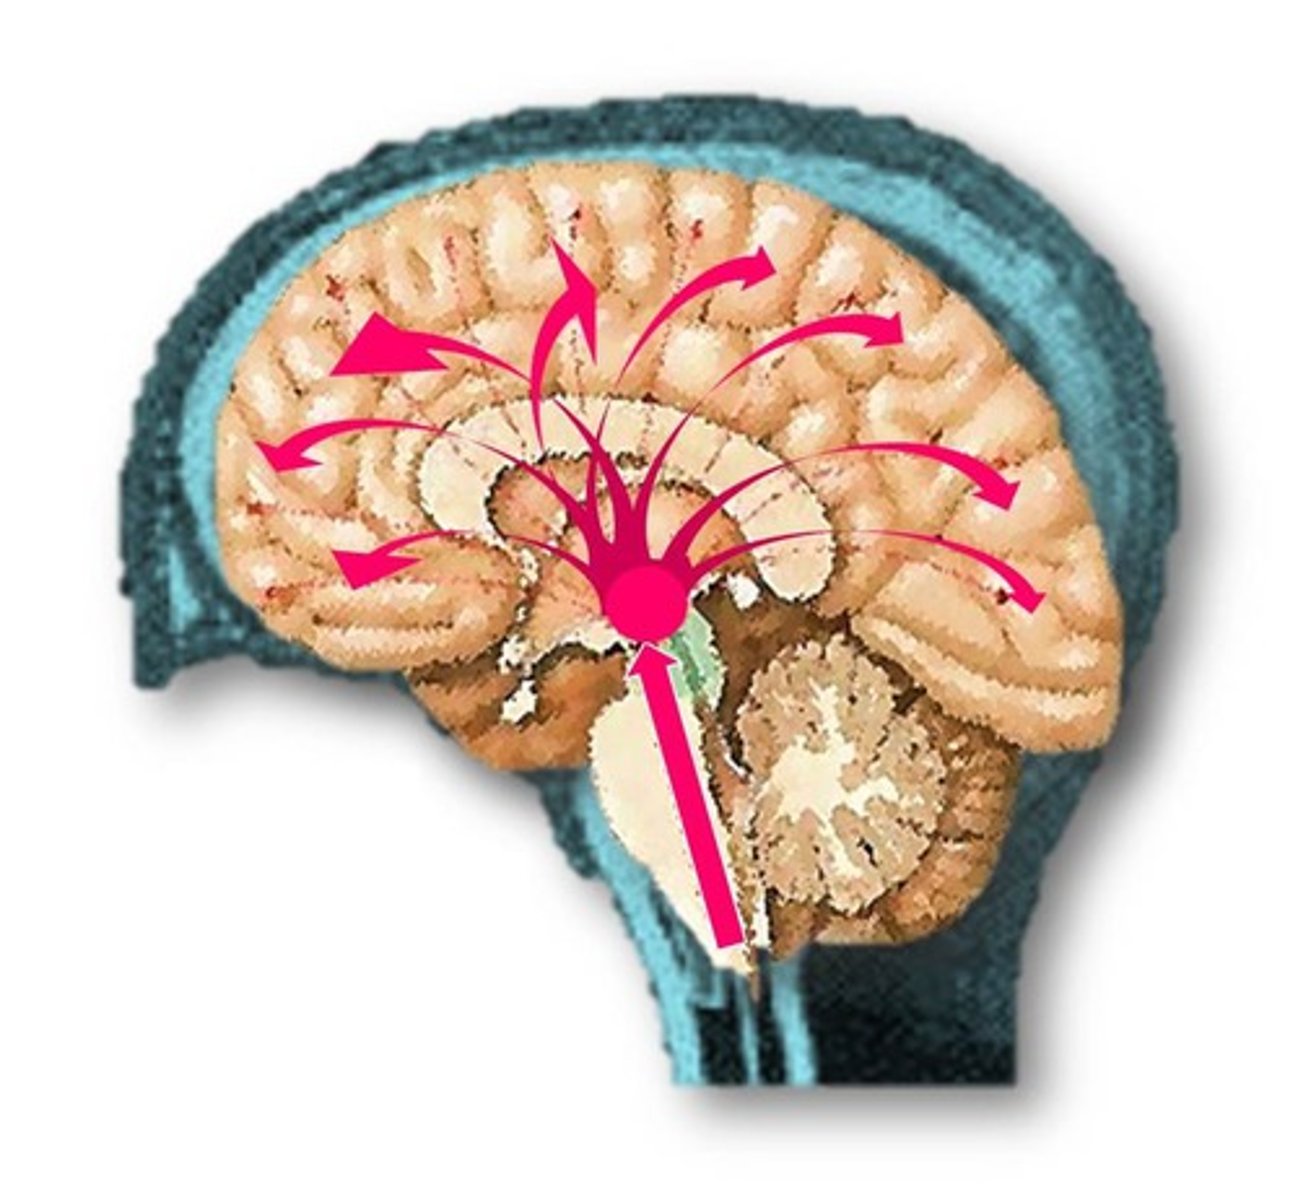

CSF production

-Brain produces and absorbs 500 mL/day

-100-160 present at one time

-produced 40% in subarachnoid space

-Produced evenly by ependymal cells lining ventricles and by the choroid plexuses

CSF creation

-Begins with filtration of blood plasma through capillaries of the brain

-More sodium and chloride then plasma

-Less potassium, glucose, and very little protein

Bouyancy

-Allows brain to attain considerable size without being impaired by its own weight

Without CSF

-If it rested heavily on floor of cranium, the pressure would kill the nervous tissue

Shock absorbtion

-Protects the brain from striking the cranium when the head is jolted

severe jolting

-cause shaken child syndrome and concussions

Chemical stability

-Flow of CSF rinses away metabolic wastes from the nervous tissue and homeostatically regulates its chemical environment